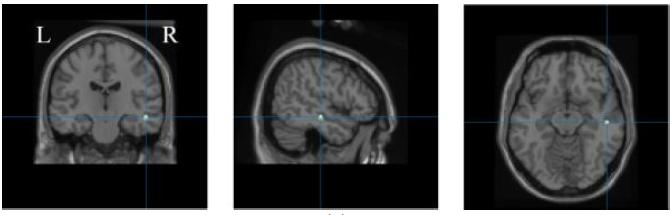

CREDIT: Yunlong ShaoCould artificial intelligence help solve the mental health crisis? What if an algorithm allowed neurologists to know the area affected by a brain seizure?

These are just two of the questions that Maryam Ravan, Ph.D., assistant professor of electrical and computer engineering, aims to address. Working on two separate studies, she proposes the use of cutting-edge algorithms and techniques that could provide noninvasive solutions for clinicians to treat neurological and psychiatric conditions more effectively.

Normal brain activity, including mood and thinking processes, relies on a balance of fast and slow brain waves. Imbalanced brain wave activity is associated with neurological issues such as epilepsy and psychiatric conditions like bipolar disorder and major depressive disorder.

One technique clinicians use to detect brain wave imbalances is electroencephalography (EEG). This diagnostic test uses sensors to measure the electrical activity on a patient’s scalp, which is representative of the brain wave activity taking place underneath. Brain wave data collected through an EEG holds valuable information regarding an individual’s neurological and mental health. Existing software models that process EEG brain wave data use a mathematical technique called exact low-resolution brain electromagnetic tomography (eLORETA).

In collaboration with McMaster University psychiatrist Gary M. Hasey, M.D., Ravan co-authored two studies that leverage machine learning, a form of artificial intelligence (AI), to improve the treatment of mental health conditions.

In one study, Ravan helped develop a machine learning algorithm to analyze patients’ brain waves and categorize their patterns as biomarkers for bipolar disorder or major depressive disorder.

The researchers pose that, given its abilities, machine learning could be useful in analyzing a patient’s EEG results and determining whether a patient is experiencing bipolar disorder or major depressive disorder. With Ravan’s expertise, the team developed a new algorithm called ReLORETA, which accounts for multiple variables known to impact brain source estimates, including head geometry and misaligned brain electrodes, among other factors.

“The accuracy of our algorithm, which was derived from a large sample of patients, successfully distinguished bipolar disorder from major depressive disorder more accurately than

the existing methods available to clinicians,” says Ravan. “This suggests that our method may hold significant promise as a clinical tool.”

A second mental health study explores how brain wave data could be used to predict how patients with major depressive disorder will respond to the antidepressant sertraline (sold under the brand name Zoloft) versus a placebo treatment.

While antidepressants are often the first line of treatment for major depressive disorder, it can take months of trial and error and multiple medications before reaching an effective treatment. If predictive biomarkers can inform how a patient will likely respond to a certain treatment, clinicians may be able to eliminate this frustrating process and fast-track a patient’s recovery time.

The study’s other co-authors include College of Engineering and Computing Sciences alumni Thomas Oakley (M.S. ’22), Jonathan Coskuner (M.S. ’21), and Andrew Cadwallader (M.S. ’22).